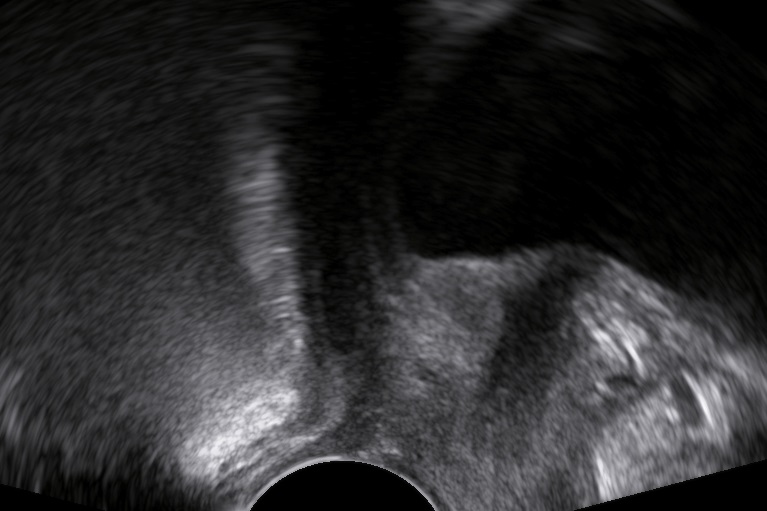

An 80-year-old female patient presents with persisting overactive bladder symptoms. After careful ultrasound examination, a unilocular cystic mass with a single urethral connecting tract containing a calculus was identified as an urethral diverticulum.

The clinician’s suspicion after acquiring a thorough patient’s history should lead to a targetted ultrasound examination combined with digital compression for possible excretion of fluid. The diagnostics may be completed with cystourethroscopy, micturating cystourethrogram, or MRI.